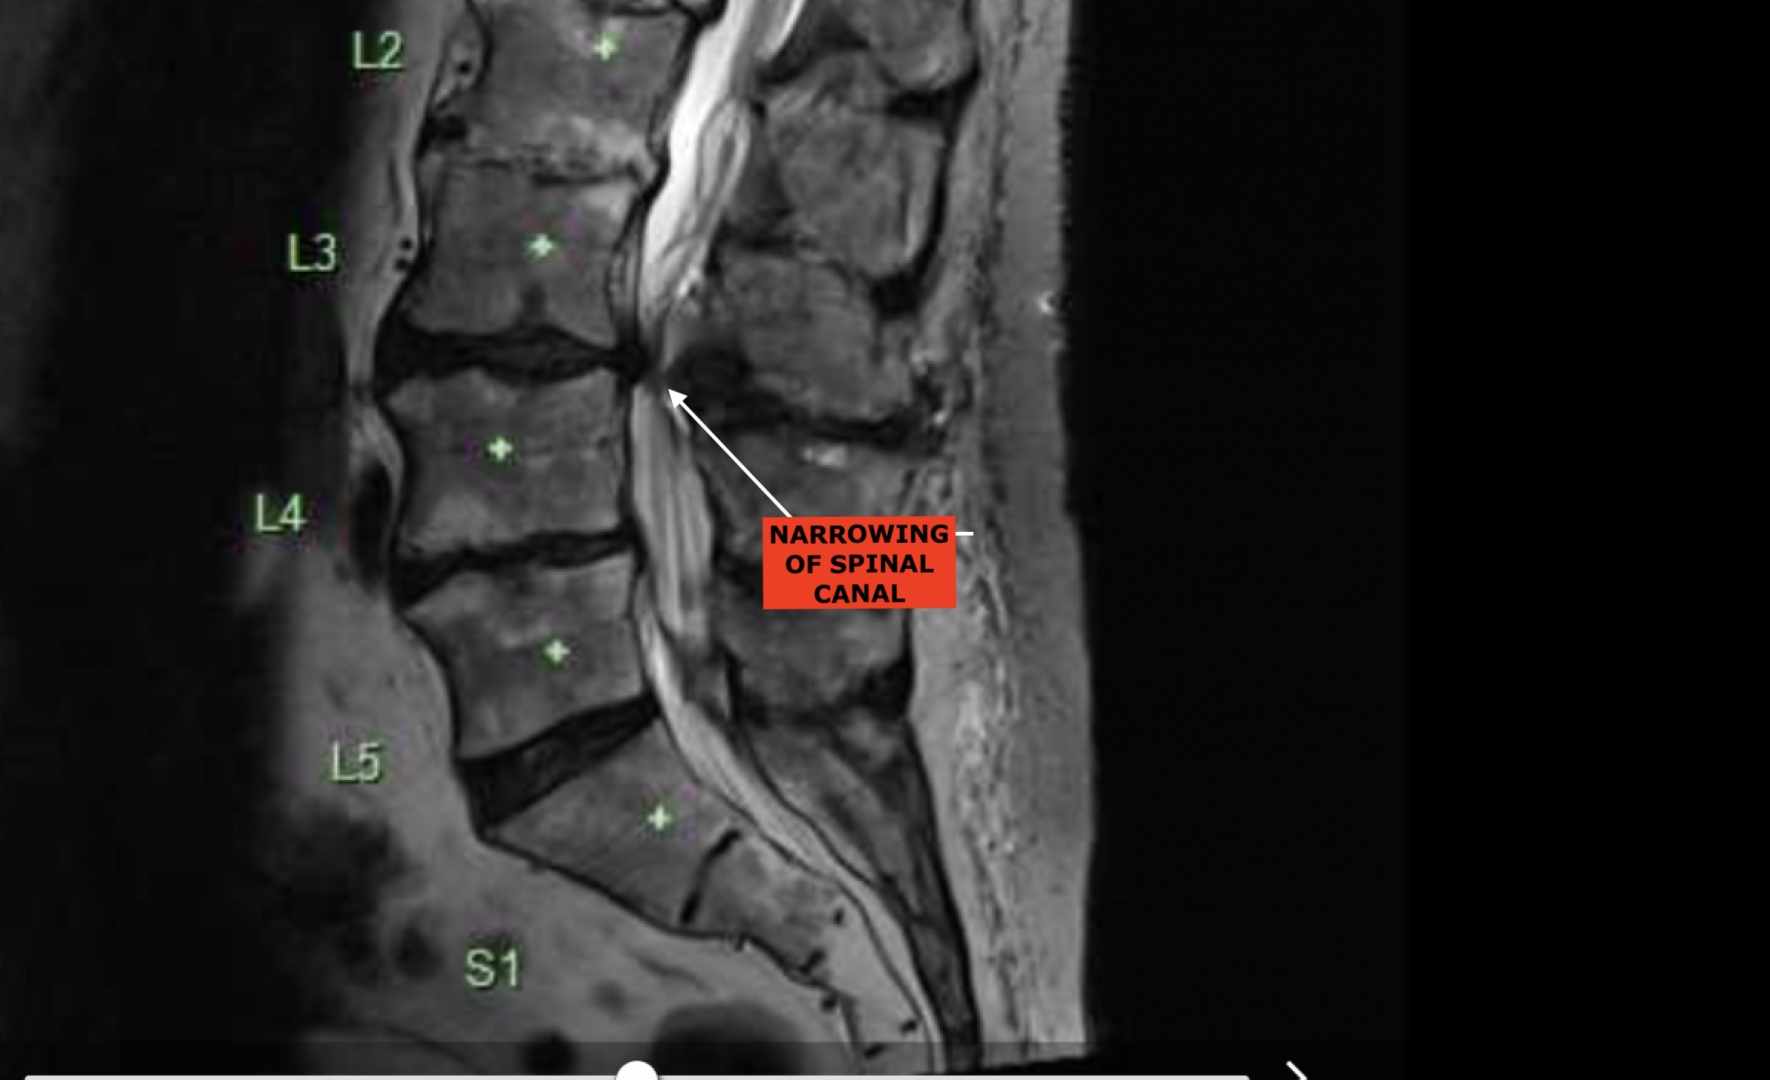

Have had the problem twice, latest was in early 2017, pain in left leg, gradually got worse to almost unbearable. To GP arranged an MRI same problem as on right leg 19 years earlier, SPINAL STENOSIS, narrowing of the Spinal Canal where the wiring harness passes through, (Spinal Cord), vertebrae pressing on a nerve.

Went to Spinal Specialist in Brisbane, (Bris Brain & Spine), who had done other side, 3 ˝ hours surgery and like new again after a couple of months. Have more flexibility now than for years.

Removed offending piece of Vertebrae, fused 2 vertebrae, inserted 6 screws and plastic cage around it all. Previous occasion was on left leg 19 years earlier and he only needed to trim vertebrae on that occasion.